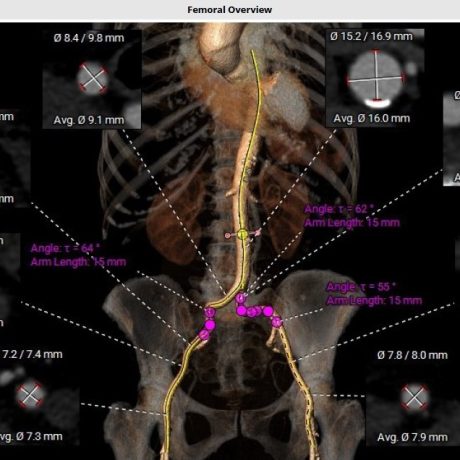

Soluciones vasculares

Portfolio técnico en intervencionismo endovascular. Implantables y consumibles para cada procedimiento.